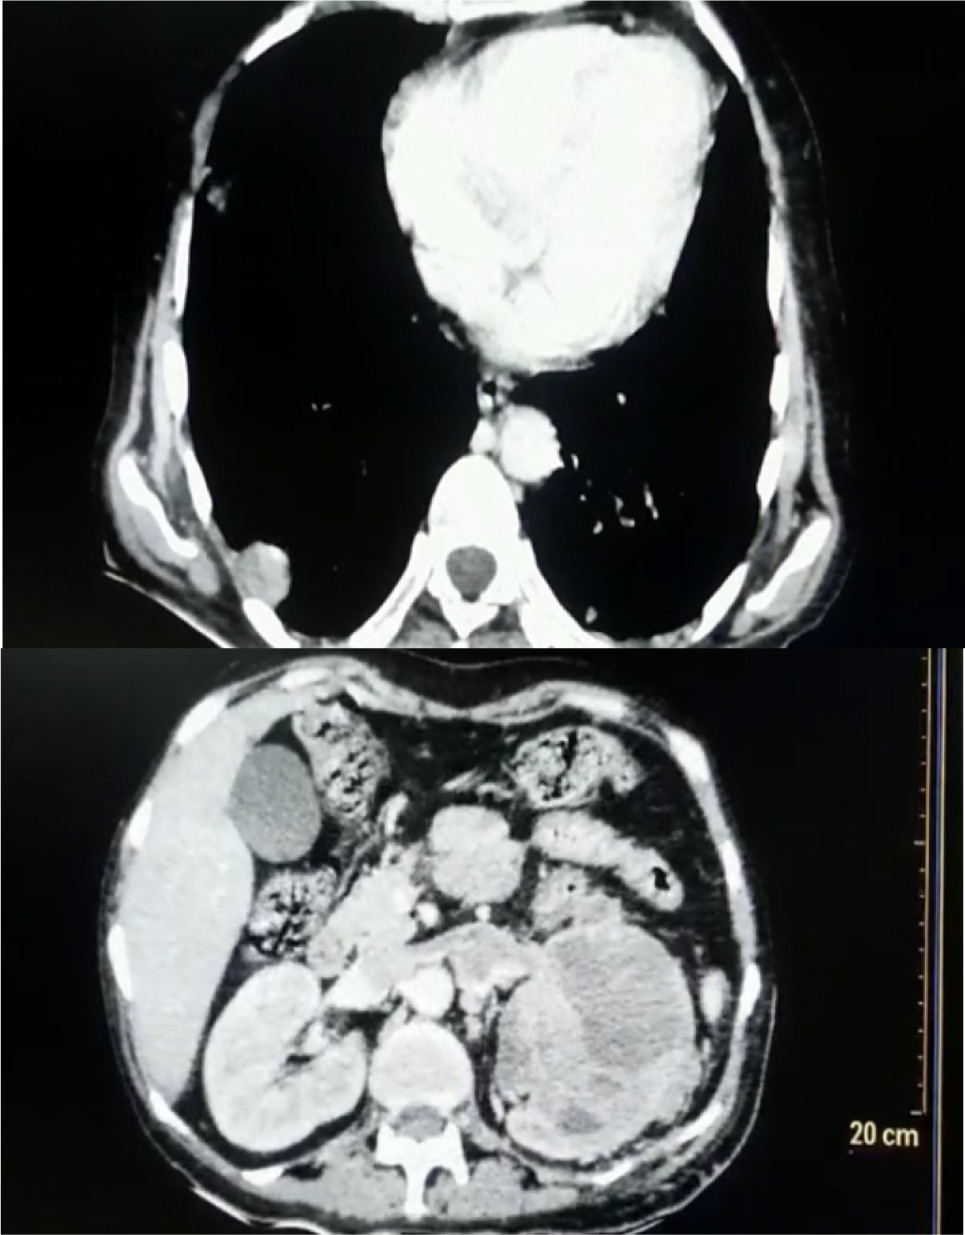

CT chest showed a pulmonary nodule on the right lung and left renal vein thrombus and a left renal mass, which was not seen on the previous CT scan (Figure 2). Decision for left radical nephrectomy was taken in view of persistent fever spikes with raised WBC counts. Open left radical nephrectomy via a thoracoabdominal approach was done. The left kidney along with the renal vein containing thrombus was removed (Figure 3).

Figure 2: Computed tomography chest with abdomen.